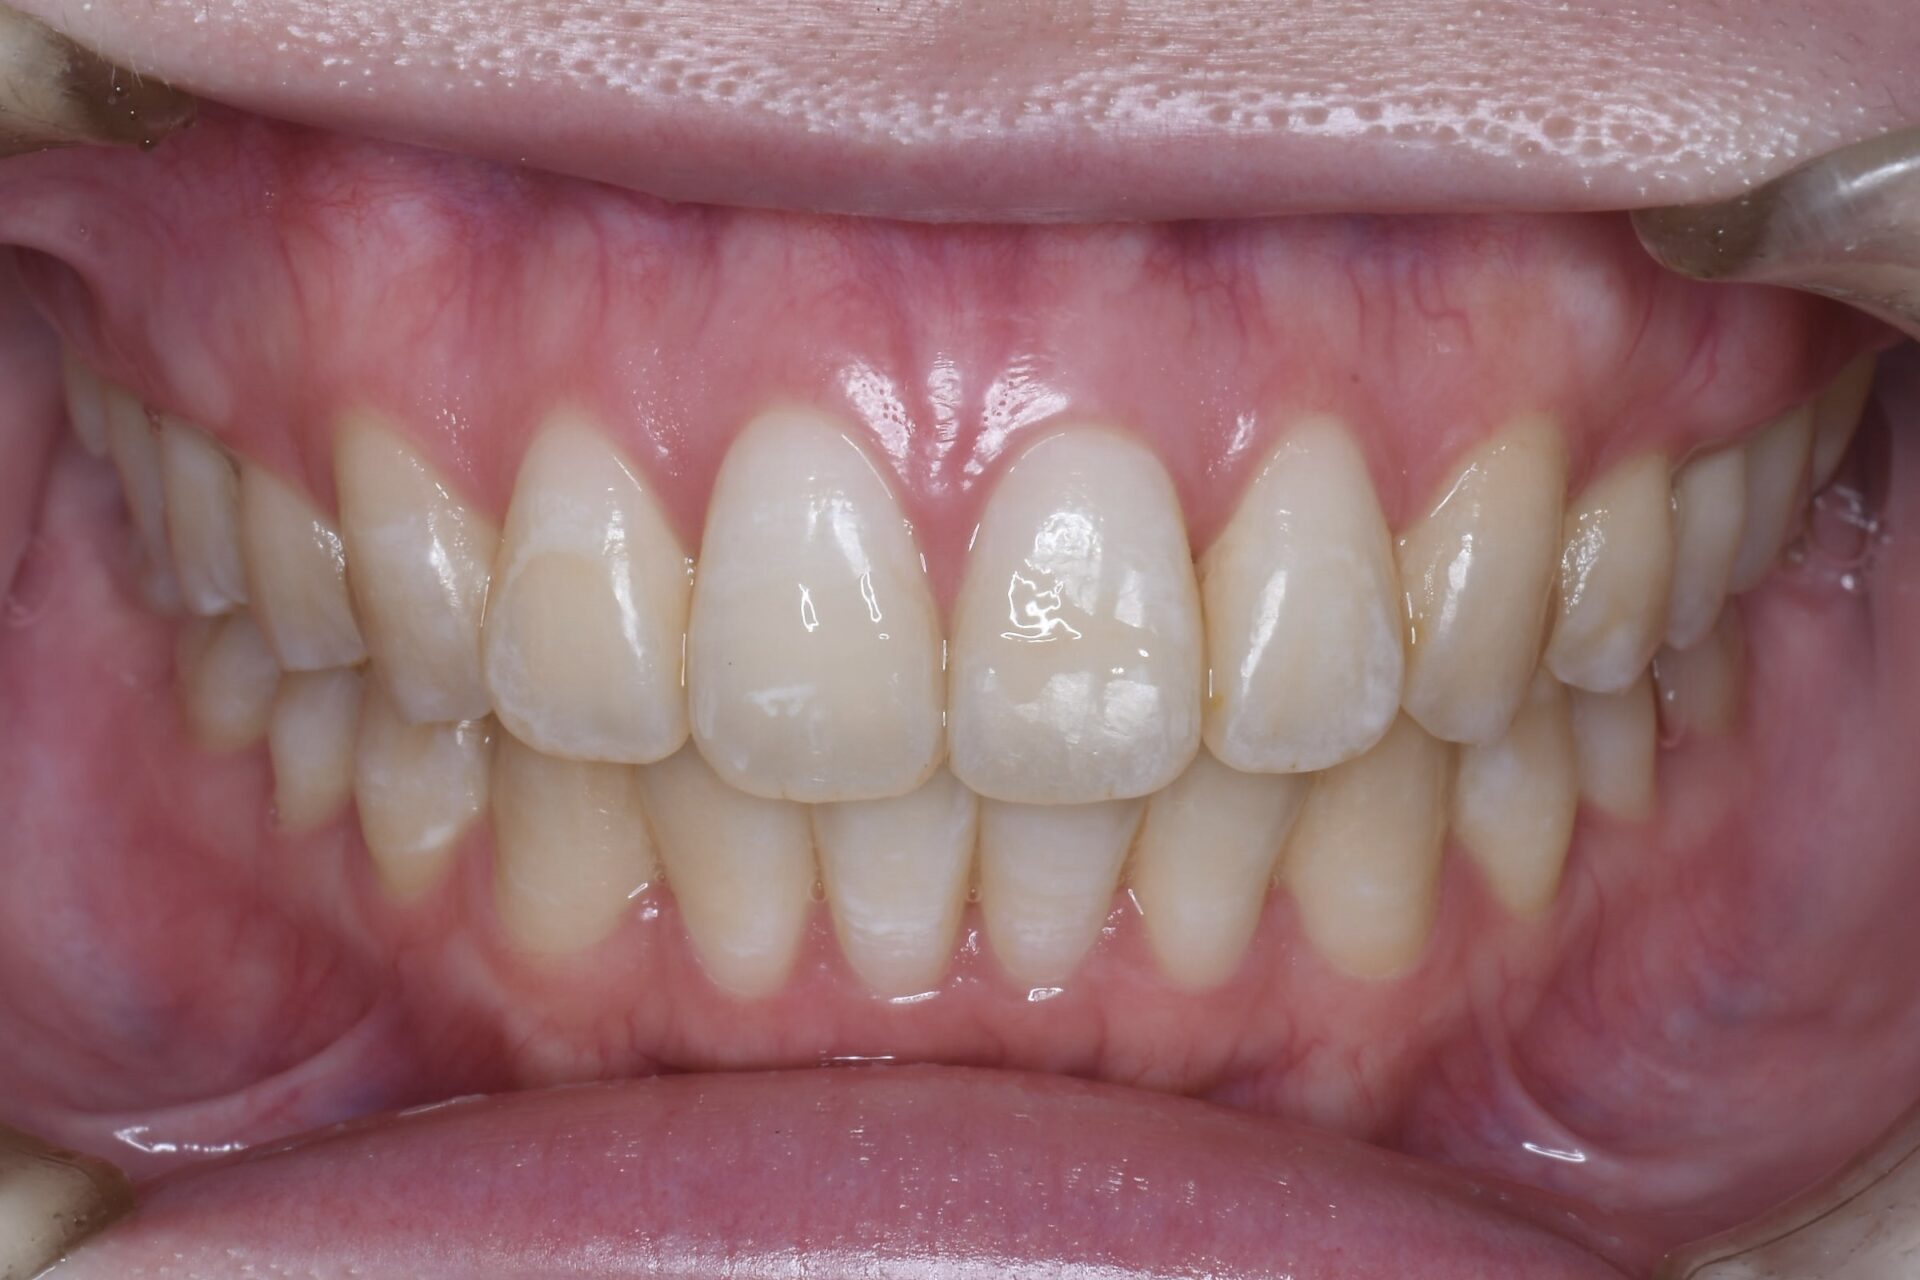

after

矯正治療終了時

矯正治療スタート

摘出部位の傷が治ってから矯正治療を再開すると、速やかに大臼歯部が内側に移動してきた。

下顎臼歯部を遠心に動かしたいが、埋伏智歯があるため動かせない。また小臼歯抜歯によりスペースを確保できたとしても開口であるため下顎の歯は並んでも上顎前歯部に下顎前歯部が届かなくなる可能性が高い。

下顎左側第2大臼歯が虫歯になっていたこと、また前歯を並べるためには臼歯部の遠心移動が必要であることを考慮し、第2大臼歯を抜歯して埋伏している親知らずを咬合参加させるように矯正治療で動かしていく。

少しずつ少しずつ。